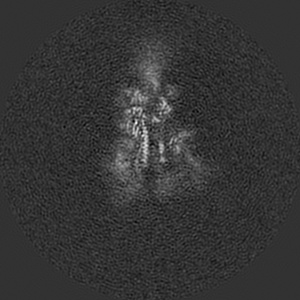

SARS-CoV-2 Wuhan Spike ectodomain in complex with NHP polyclonal antibody NVX-NHPSA5 (NVX-CoV2373/rS-Beta immunized)

Single-particle4.5 Å

Sample: SARS-CoV-2 Wuhan spike ectodomain in complex with NHP polyclonal antibody NVX-NHPSA5